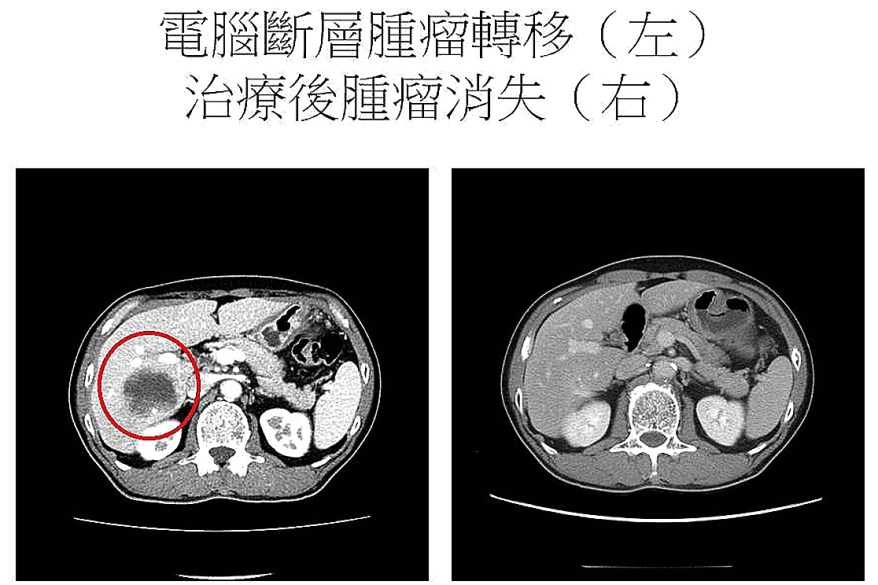

面對已無法手術的胃癌晚期,余政展主任針對HER2陽性胃癌型態,建議林先生接受化療合併抗HER2標靶藥物,結果治療效果良好,林先生胃癌細胞消失,肝轉移只剩些許痕跡,但也因為藥物自費金額一年逾百萬元,負擔過大而選擇停藥。余政展主任指出,有些HER2陽性胃癌病人也因為同樣的原因無法接受適當治療,徒留遺憾。林先生很幸運,HER2陽性胃癌標靶藥物納入健保給付後,已開始重新接受治療,大幅減低經濟負擔。